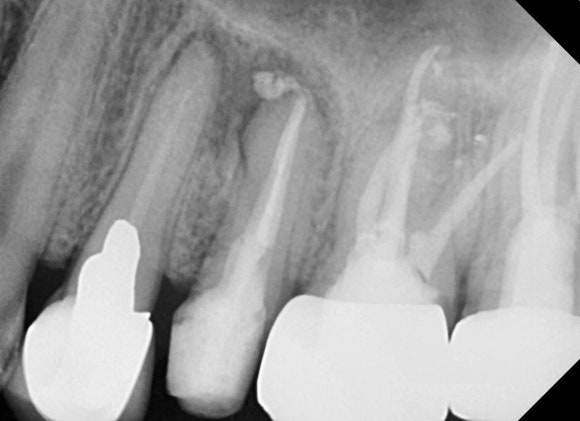

20240411

치료 전 사진입니다.

이전에 신경치료한 것이 약간 허술해보입니다.

옛날에는 영상 기술이나 기구, 재료가 지금만큼 우수하지 못했기 때문입니다.

그러나 구강 내에서 수년을 불편감없이 버텨냈습니다. 십년을 넘게 쓰시는 경우도 심심치않게 보입니다.

엑스레이상으로 어떻게 보이느냐보다는

실제로 환자분의 불편감과 이어지느냐가

재신경치료를 할지 말지를 결정한다고 보시면 되겠습니다.